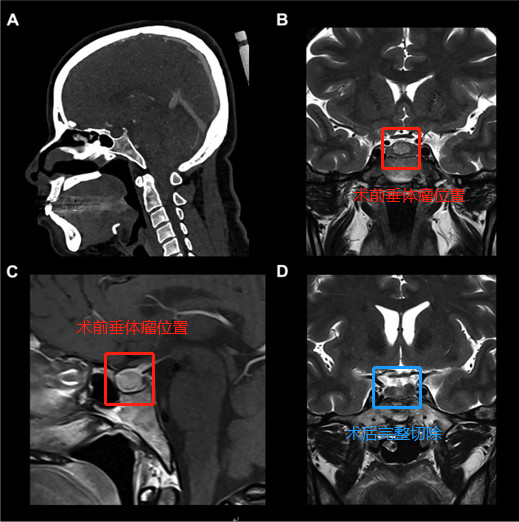

神经外科手术中导航可以帮助发现关键结构和目标病灶。本文探讨经鼻经蝶窦切除垂体瘤术中立体定向计算机断层扫描(CT)的顺利性和合适性...